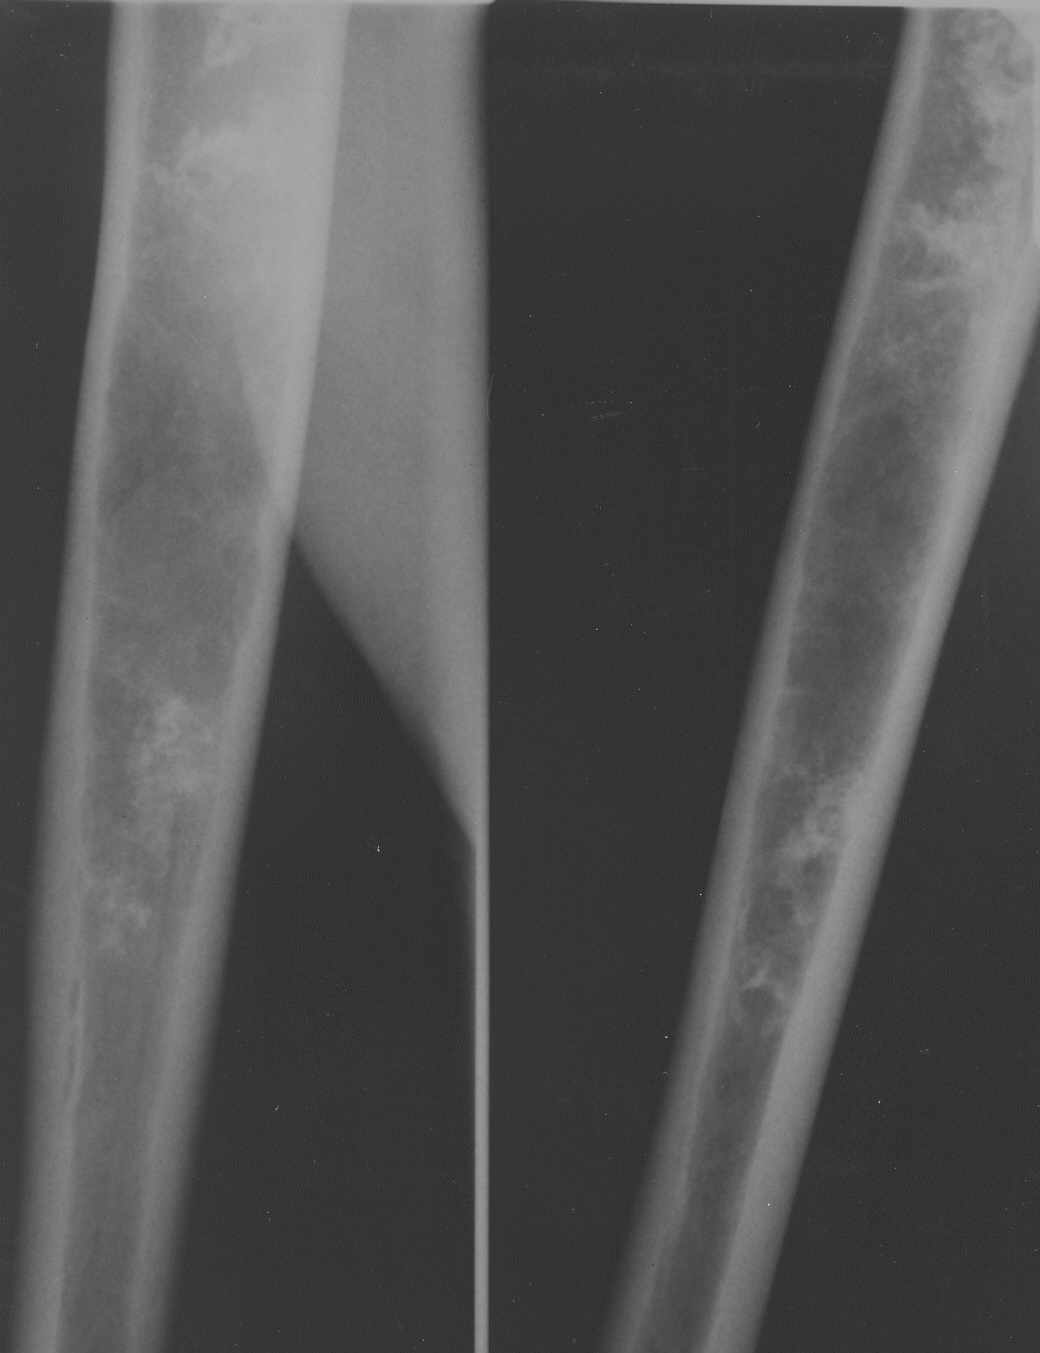

Обратился пациент с жалобами на боли в области плечевого сустава.

Боли беспокоят при движениях (поднятии руки, заведении руки за спину). В покое боли не

беспокоят. Кроме болей ни субъективно, ни клинически никаких данных. Получены вот такие

рентгенограммы:

Имя     : rentgen2.jpg

Размер  : 26655 байтов